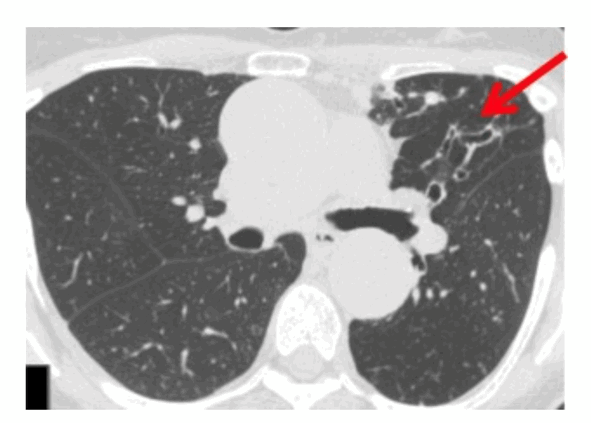

Узловая бронхоэктатическая болезнь легких обычно проявляется у пожилых, худых женщин и сопровождается воронкообразной деформацией грудной клетки, сколиозом и пролапсом митрального клапана. Узловые бронхоэктазы могут визуализироваться на рентгенограмме грудной клетки как «трамвайные следы» с микроузелками, но лучше всего они видны во время компьютерной томографии грудной клетки с высоким разрешением. На КТ бронхоэктазы имеют цилиндрическую форму с ветвящимися центрилобулярными узелками («дерево в зародыше»). Эти изменения обычно двусторонние, но преимущественно затрагивают язычковую и правую среднюю долю.

На компьютерной томографии органов грудной клетки с высоким разрешением видны узловые бронхоэктазы, которые поражают язычковую долю. Источник

В целом эти рентгенологические признаки также неспецифичны и могут наблюдаться при аспирации и других бактериальных инфекциях.